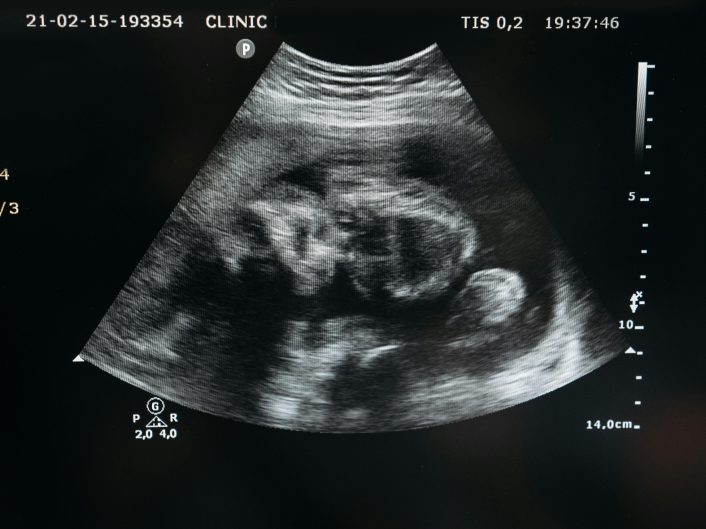

La negligencia en obstetricia ocurre cuando se omiten controles, diagnósticos o intervenciones necesarias durante el embarazo, parto o puerperio, provocando lesiones a la madre o al bebé.

La paciente debe estar informada del plan de parto, riesgos y alternativas. La monitorización fetal durante el trabajo de parto debe ser constante, y cualquier omisión puede ser reprochable.